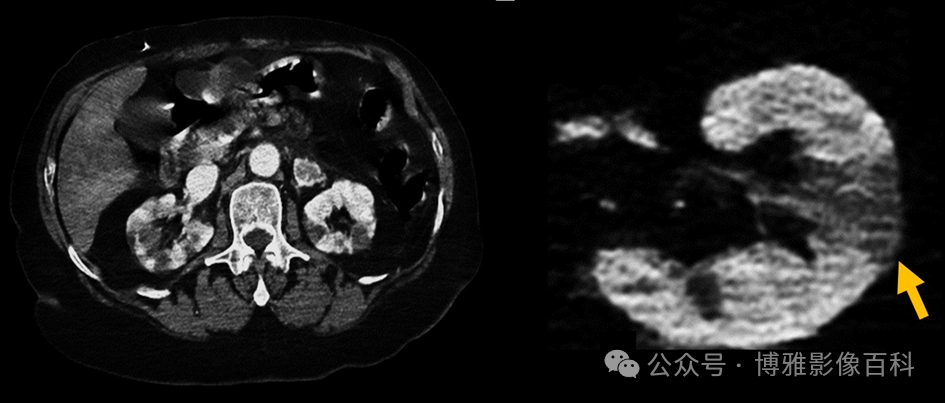

肾血管形成:肾动脉逐渐分叉为节段动脉、叶间动脉、弓状动脉和肾小叶间动脉。在到达肾门之前,肾动脉会发出与肾上腺动脉、性腺动脉、腰动脉或膈下动脉吻合的包膜动脉,形成肾周动脉网。

肾缺血:

原因:栓塞、血栓形成、主动脉或肾动脉夹层、血管炎、外伤、休克、医源性(手术、介入手术)

影像表现:梗死的外观取决于闭塞的位置:

肾动脉实质内分支:楔形低密度,顶点位于远端梗阻处,基底部朝向皮质

892f58a7ed00c9c329c0f8526ec46b52.png

图16:CT门静脉期。楔形肾梗死肾动脉:实质广泛性弱强化或无增强,肾脏大小增加 (由于水肿) 和排泄不足

509af20860f14e437ce46f61e49265fe.png

图17:CT门静脉期。弥漫性肾梗死在大面积梗死中,由于侧支循环,6-8小时后(亚急性期)通常出现“皮质边缘征”(箭头)。